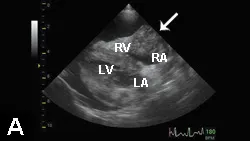

Imaging & Laboratory ResultsA peripheral catheter was placed and shock fluid therapy initiated, followed by ultrasound-guided pericardiocentesis; this resulted in immediate clinical improvement. Following stabilization, staging tests for suspected hemangiosarcoma were performed. No visible metastatic disease was identified on thoracic radiographs and abdominal ultrasound (Figure 2).

Figures 2A, 2B & 2C. Thoracic radiographs (A, B) and abdominal ultrasound (C) failed to identify any visible metastatic disease.